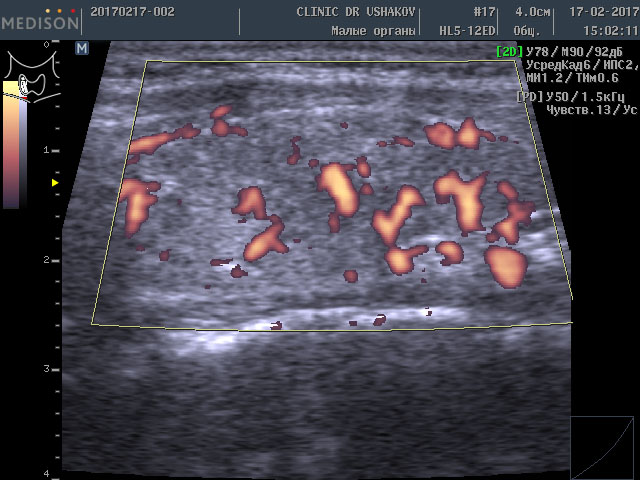

Ошибочно думать, что при таком сильно выраженном дефиците щитовидных гормонов (Т3 и Т4) щитовидная железа ослаблена и её «функция снижена». Ультразвуковое исследование показало, что объём железы почти нормальный 12,7 мл (даже немного индивидуально увеличен), а кровоток значительно усилен (рис. 5 и 6). Сравните насыщенность кровотока (по выраженности красных участков) с приведенными ранее примерами.

Рисунки 5 и 6. Пациентка К., 45 лет, левая и правая доли щитовидной железы в режиме ЭДК. Кровоток (обозначен красным цветом) в значительной степени усилен (Такое состояние сосудистой сети характерно для гипертиреоза ― повышения функции щитовидной железы»).

Заметно более выраженное кровообращение, которое прямо указывает на соответствующую значительную нервную стимуляцию ткани железы и её сосудов (одновременное сильное влияние со стороны нервных центров на ткань железы и кровоток). Это признак очень интенсивного перенапряжения щитовидной железы. Именно такая картина наблюдается при УЗИ в случае гипертиреоза ― избыточной продукции гормонов щитовидной железой, т.е. состоянии, которое называется врачами «повышение функции щитовидной железы». Это доказывает, что гипотиреоз ― усиление функционального напряжения щитовидной железы (Под влиянием ТТГ и нервных стимулов щитовидная железа избыточно и значительно перенапрягается для обеспечения организма достаточным количеством гормонов, потребление которых увеличивается при неблагоприятных условиях; только в нашей Клинике дано пояснение усилению кровотока в ЩЖ при гипотиреозе).